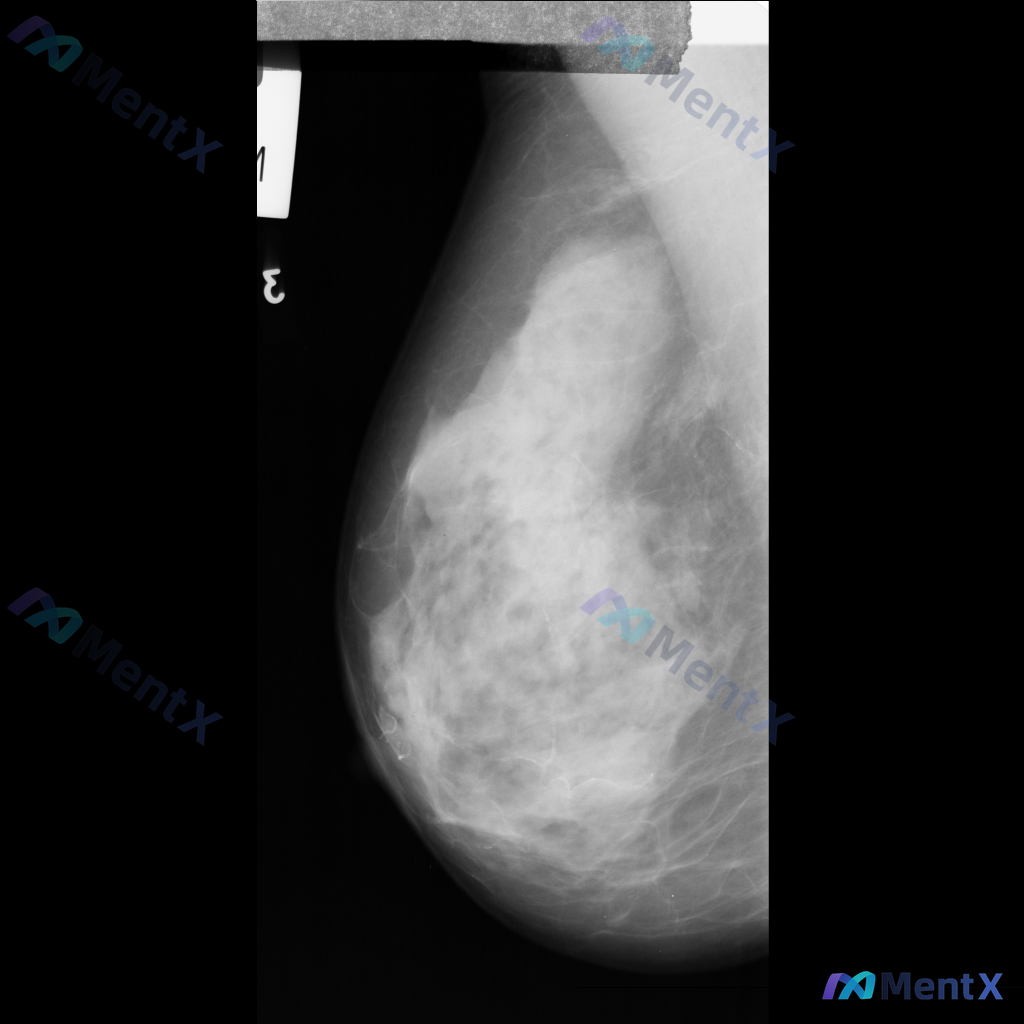

- 投照位置:单侧乳腺MLO位

- 主要表现:乳腺组织不均匀致密,ACR BI-RADS c类;在致密的腺体背景下,可见部分区域的致密影,但边界比较模糊,暂不能明确界定为独立肿块。